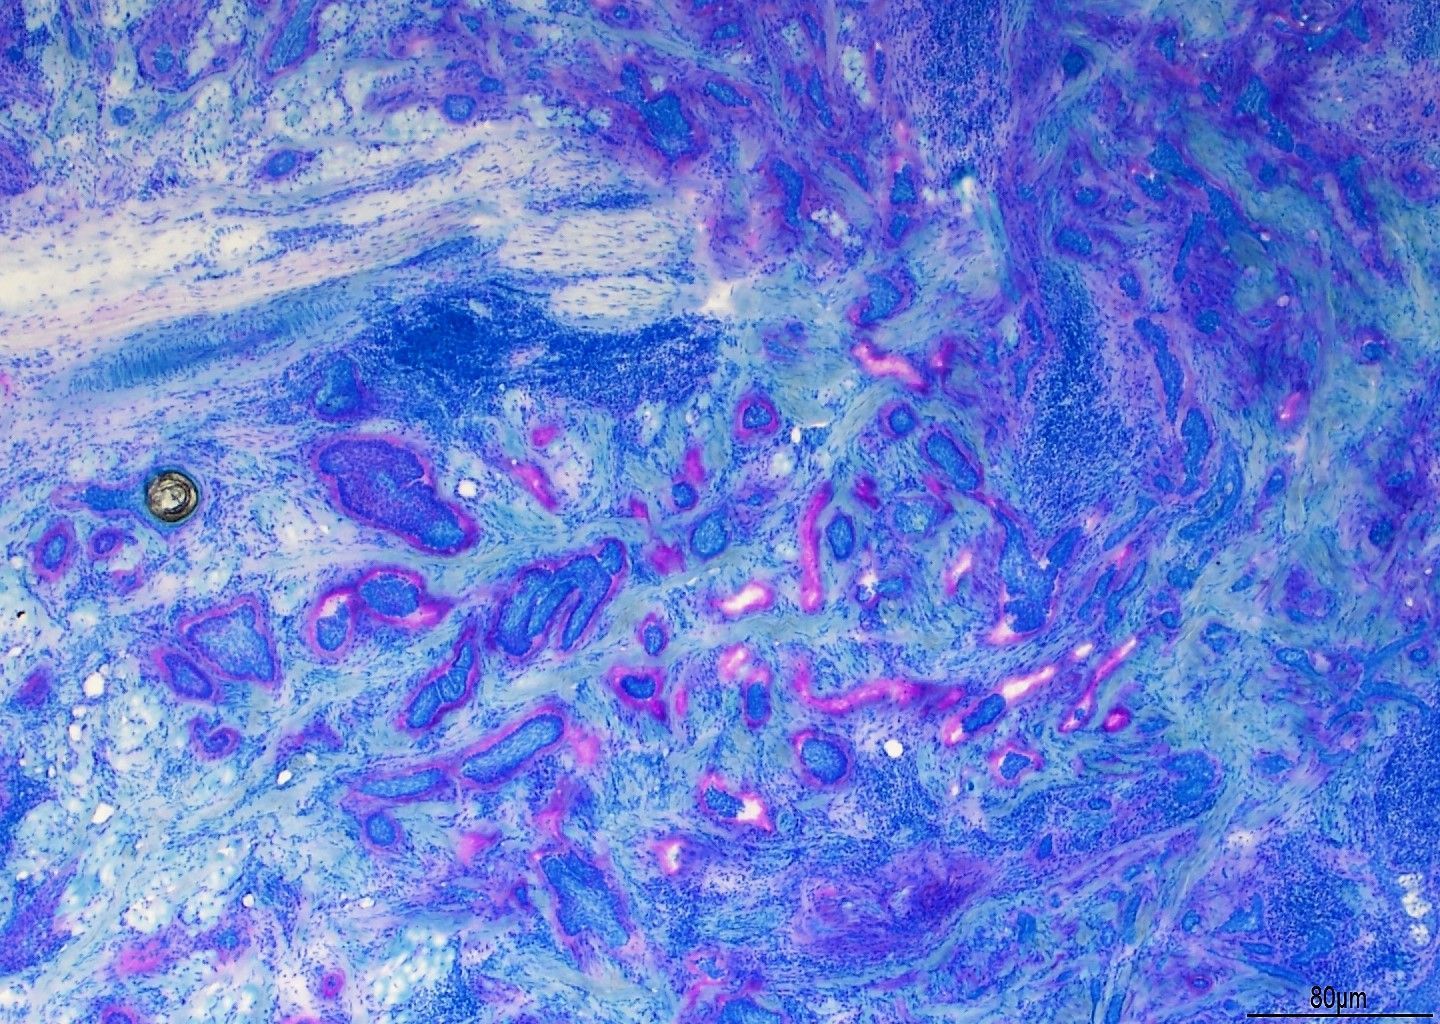

- ਅਨੁਕੂਲ ਅਤੇ ਉਪ-ਅਨੁਕੂਲ ਰੰਗਾਈ ਦਿਖਾਉਣ ਵਾਲੇ ਰੰਗ ਚਿੱਤਰਾਂ ਦੀ ਔਨਲਾਈਨ ਲਾਇਬ੍ਰੇਰੀ